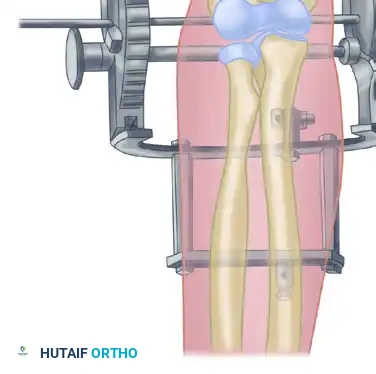

2. Hinged External Fixation

Many contemporary orthopedic surgeons prefer the application of a hinged external fixator. Although technically more complex and resource-intensive, a hinged fixator maintains concentric joint reduction while allowing immediate, guided range of motion. This theoretically improves cartilage nutrition, reduces intra-articular adhesion formation, and optimizes functional results.

Surgical Pitfall: The axis of the hinged external fixator must perfectly align with the anatomical axis of elbow rotation (passing through the center of the capitellum and the anteroinferior aspect of the medial epicondyle). Malalignment will lead to eccentric loading, subluxation, and rapid pin loosening.